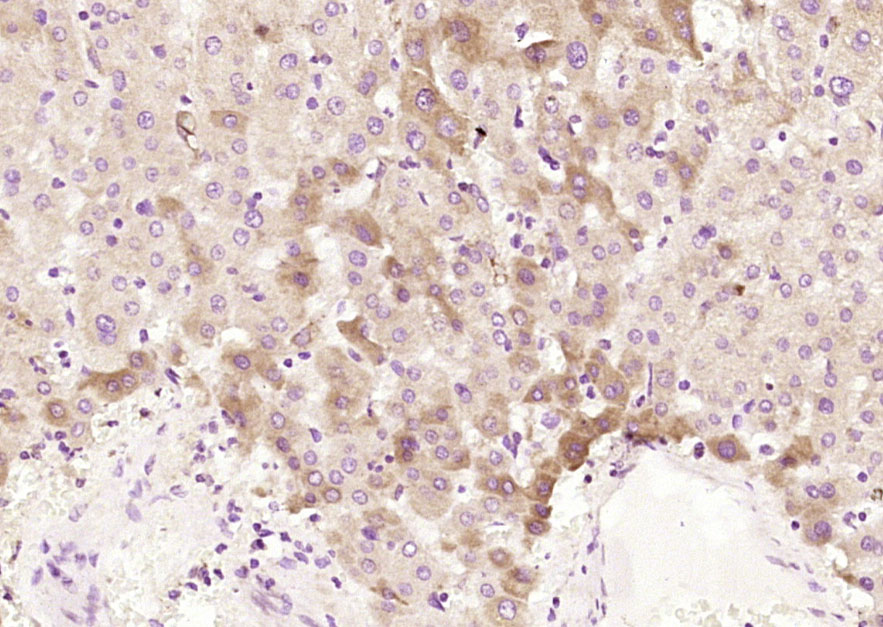

Paraformaldehyde-fixed, paraffin embedded (human liver); Antigen retrieval by boiling in sodium citrate buffer (pH6.0) for 15min; Block endogenous peroxidase by 3% hydrogen peroxide for 20 minutes; Blocking buffer (normal goat serum) at 37°C for 30min; Antibody incubation with (ACADM) Polyclonal Antibody, Unconjugated (bs-4047R) at 1:200 overnight at 4°C, followed by operating according to SP Kit(Rabbit) (sp-0023) instructionsand DAB staining.